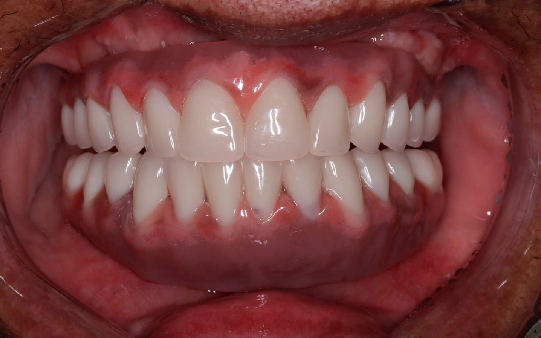

Protocolo em Resina Acrílica: boa estética, acessível, indicado para reabilitações com ótimo custo-benefício.